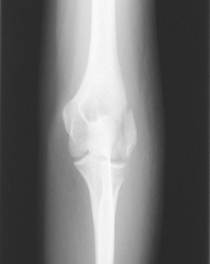

図8 a 図8 b

第24診時のレントゲン斜位像 第24診時のレントゲン正面像